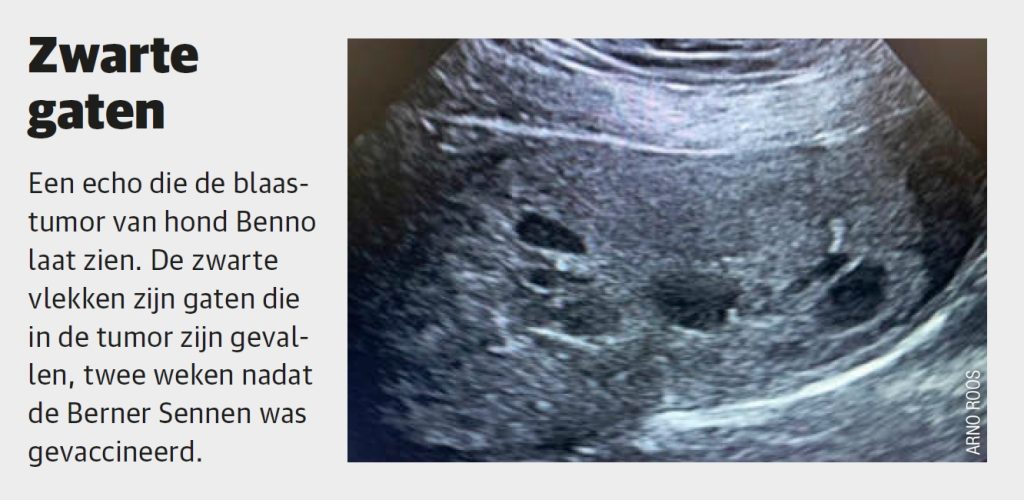

De eerste resultaten in honden zijn veelbelovend. Griffioen werkte samen met dierenartsen die honden met kanker in hun praktijk kregen en zag dat bij alle veertig behandelde honden de tumor kleiner werd of in zijn geheel verdween. “Ons bekendste voorbeeld is Benno de Berner Sennenhond. Hij had een grote tumor in zijn blaas en een slechte prognose. We mochten hem inenten met ons experimentele vaccin en twee weken later vielen er al gaten in de tumor.” Dat was drie jaar geleden. Inmiddels leeft Benno nog steeds kankervrij en is hij twaalf.